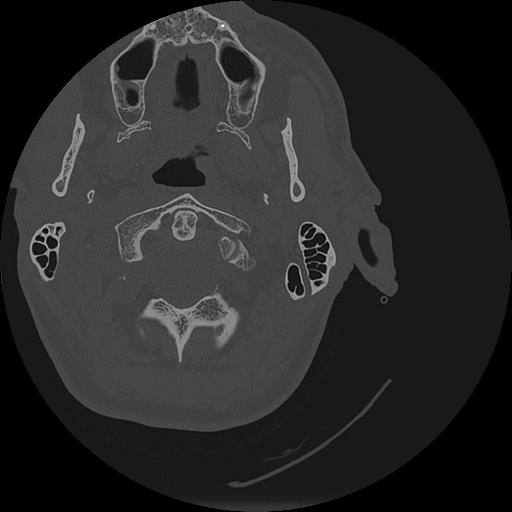

7 HUESO,,Vol,0.5,HUESO,,